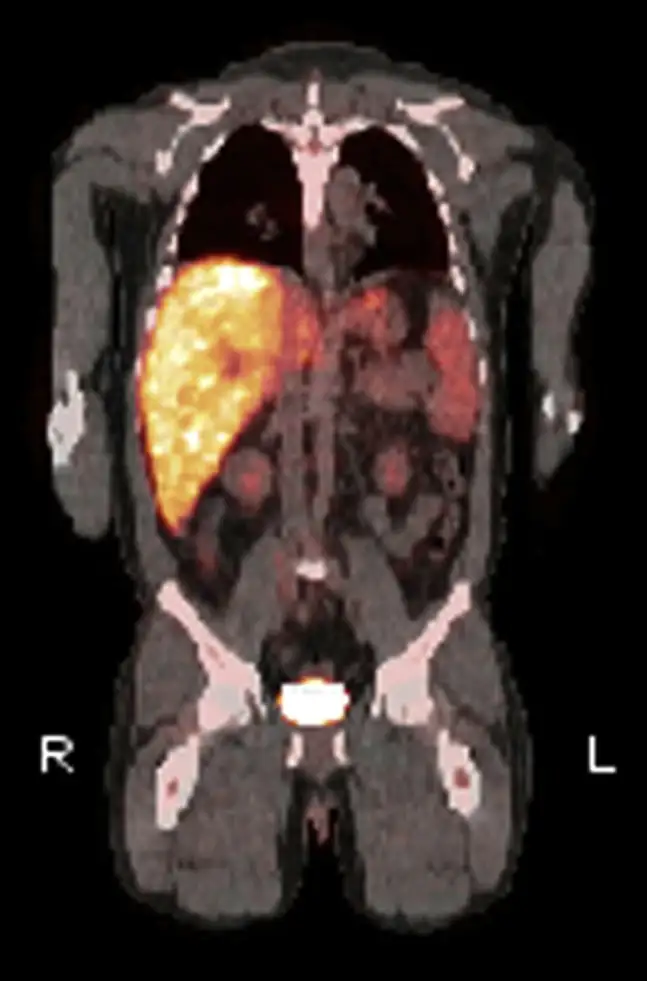

然而,Q热真正令人恐惧的并非急性期,而是它的慢性化。大约1%到5%的急性感染者在数月甚至数年后会发展为慢性Q热,这是一种完全不同的疾病。病原体在体内潜伏,等待机会,最终在一些特定的部位——通常是心脏瓣膜——建立慢性感染。慢性Q热心内膜炎是最常见也最致命的表现。它发展缓慢、隐匿,患者可能只是感到疲劳、体重下降、低热、关节痛,这些症状被归咎于其他原因,直到心脏瓣膜被严重破坏。

慢性Q热心内膜炎的病死率令人震惊:未经治疗的患者,病死率高达25%到60%。即使接受治疗,患者也需要服用抗生素长达18个月到数年,甚至终身。治疗方案通常是多西环素联合羟氯喹,后者可以碱化吞噬溶酶体,削弱细菌的酸性生存优势。这种治疗可以显著降低病死率,但副作用也不容忽视——长期服用多西环素可能导致光敏性皮疹和牙齿变色,羟氯喹则有视网膜毒性的风险。

更令人不安的是,慢性Q热可能在感染数十年后才出现症状。有报道记录了患者在急性感染后20年才发展为心内膜炎的案例。这意味着,那些曾在某个不知名的时刻感染过Q热的人,体内可能潜伏着一个定时炸弹,等待着免疫系统减弱或其他触发因素的出现。